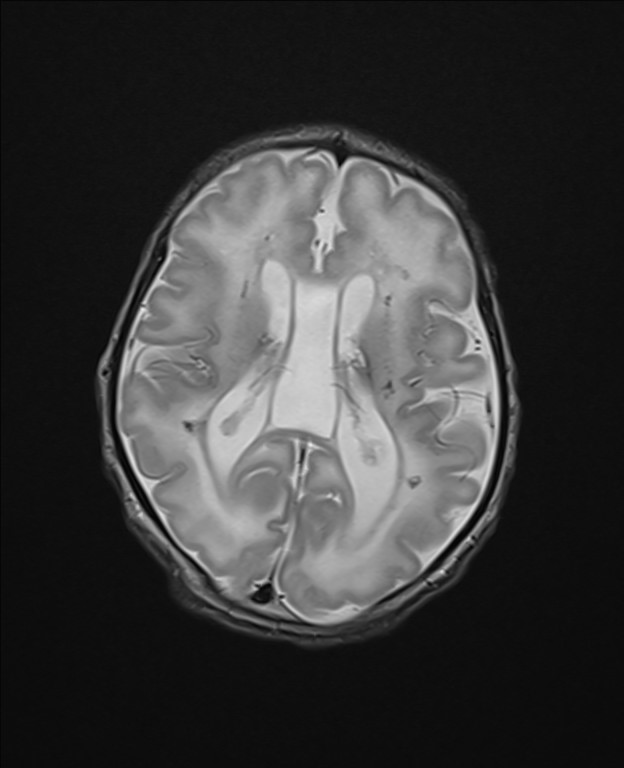

En el corte axial de la RM cerebral (Fig. 1C y 1D) se aprecia un aumento de señal de sustancia blanca con una ventriculomegalia y un quiste de septum enorme.

Figura 1C. RM cerebral. Corte axial en T1-WI.